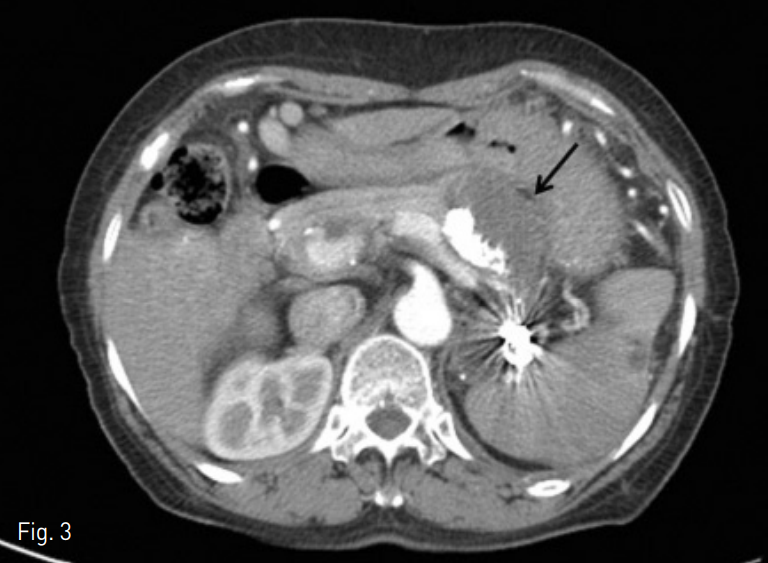

Fig. 3

A contrast enhanced axial CT image obtained 3 month later shows complete thrombosis of largest splenic artery aneurysm (arrow) with multiple embolic materials.